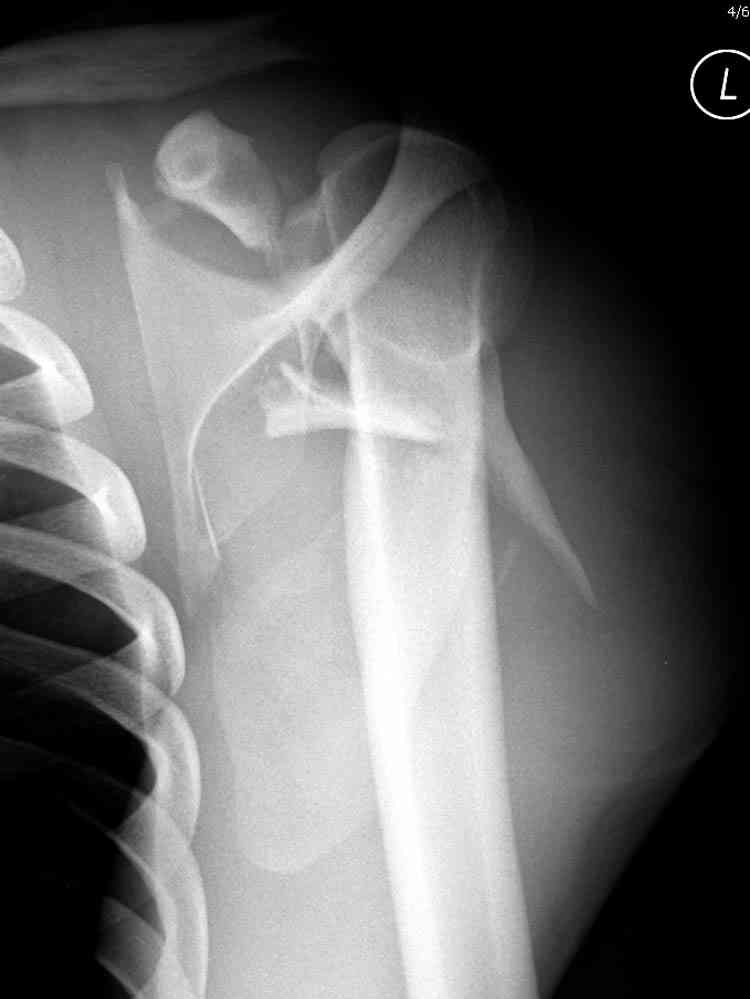

Для решения насчет оперативного вмещательства на лопатке сперва надо определиться с обьязательными ренгенологическими исследованиями, не менее трех стандартных проекций: прямая, аксиллярная и в позиции виде “Y”.

Прямую снимают под углом в 35 градусов от центра и вид “Y” в 90 градусов к нему. Несмотря на неудобства, больному необходимо сделать

аксиллярный снимок.

Нестабильные внесуставные переломы лопатки типично сочетаются с переломами ключицы и ребер.

Сочетания в результате скоростных травм приводят к нестабильности плечевого пояса, и имеют тенденцию ротироваться кнутри, в результате чего возможны повреждения плечевого сплетения.

При отсутствии соединения верхнего пояса с телом из-за перелома ключицы и шейки лопатки имеется состояние "floating shoulder", как в аналогии повреждения около коленного сустава "floating knee" при переломах костей выше и ниже коленного сустава.